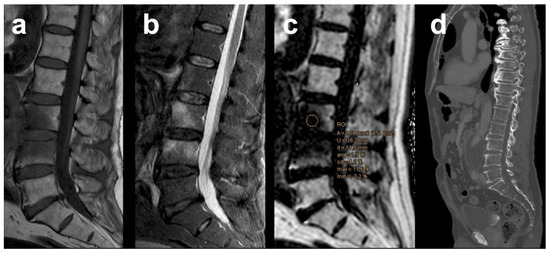

| PDFF | % | 35.29 | 17.15 | 4.28 | 3.12 | <0.001 * |

| PDFFratio | 0.67 | 0.37 | 0.093 | 0.059 | <0.001 * | |